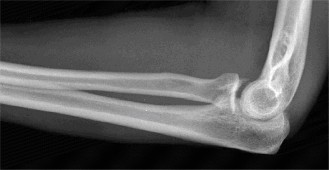

any activity in which the arm is extended and externally rotated while under maximal contraction (eccentric loading force). Patients often present with pain, swelling, ecchymosis, weakness and loss of the axillary fold in the acute setting. In the chronic setting, the swelling and ecchymosis have typically subsided. They may report an audible pop or a tearing sensation. On examination, there can be an apparent continuous muscle or tendon that is mistaken for an intact PMM tendon, but this represents the fascia of the PMM that is continuous with the fascia of both the brachium and the medial antebrachial septum. This continuous fascia will examine as a cord-like structure as shown in Figure 2–78.

Figure 2–78